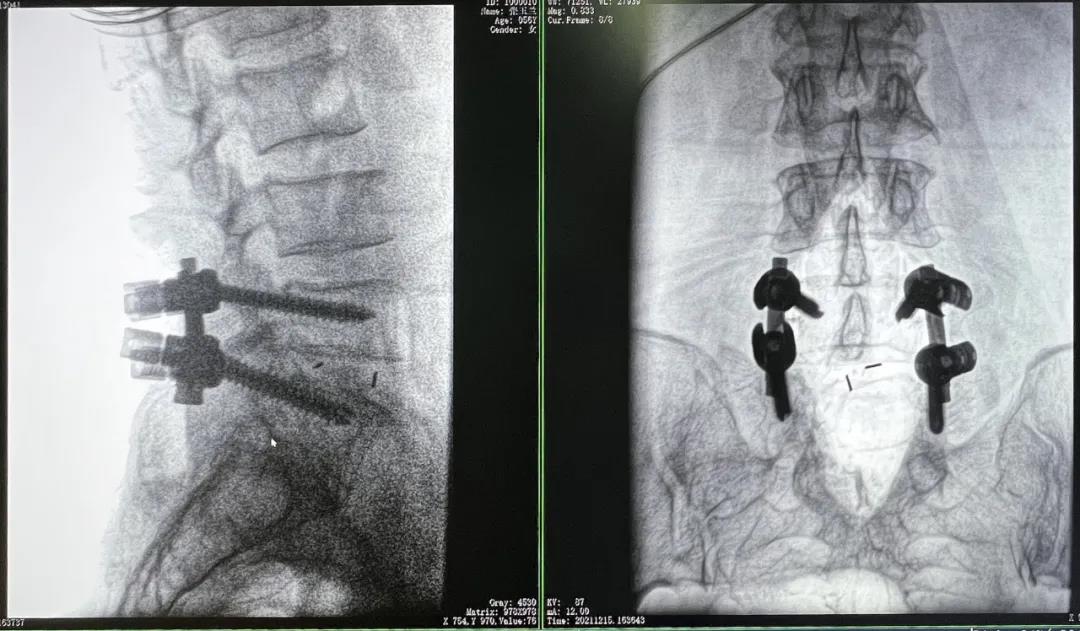

3D C形臂擺位及手術前二維影像

醫生在影像引導下在L5/S1椎弓根處打入醫用螺釘